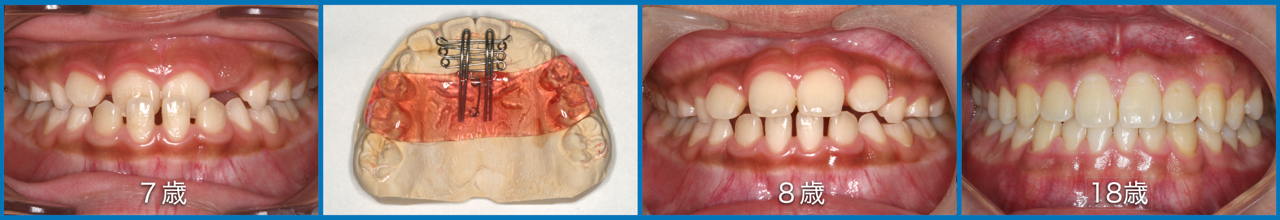

子供達を健康で綺麗な歯並びの永久歯列に誘導していくことを咬合育成と言います。開業時から来院していた子供達を見ていて、どうしたら綺麗な歯並びにできるのかを研究してきました。最近その成果が上がるようになり多くの子供達が健康できれいな歯並びをもった大人になって来院するようになっています。対外的にも「講演・論文」のページにあるように各地の歯科大学や歯科医師会からその分野の講演を依頼されるようになり、いつのまにか須貝歯科医院の得意分野になってしまいました。永久歯への生え替わりの時期が最も重要な時期です。簡単な装置で歯並びを改善していくのですが患者さんによっては矯正専門医に紹介しなければならないケースもあります。その時は地元の信頼できる矯正専門医をご紹介しています。

上の前歯は下の前歯より前にないといけませんが、前歯の生え替わりの時に1本逆に生えてきました。そのままではきれいな歯並びにはなりそうもありません。この時が治療のタイミングです。簡単な矯正装置で改善しただけでその後きれいな永久歯列になりました。